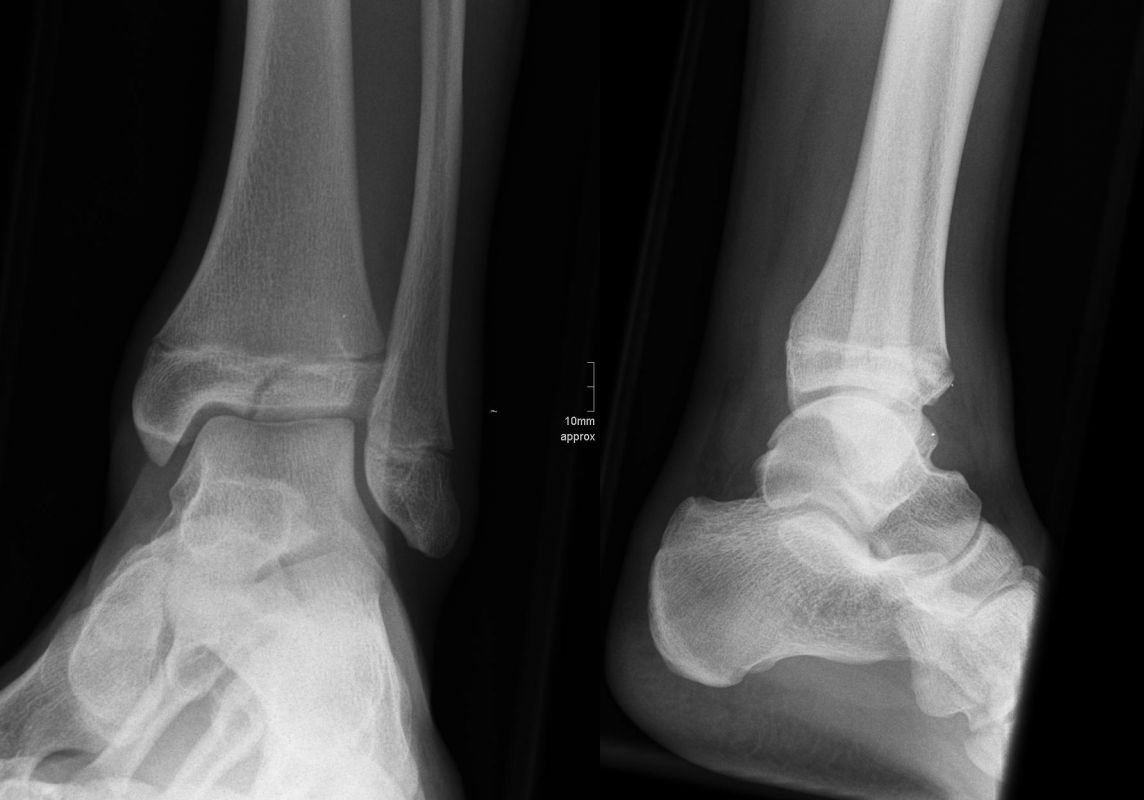

Die Standard Röntgendiagnostik des Sprunggelenks umfasst Bilder in anteriorposterioren (a.p.) und im seitlichen Strahlengang 6. Für die exakte Abbildung des Innenknöchels müssen beide Malleolen parallel zur Röntgenplatte zu liegen kommen. Je nach Torsion der Tibia macht dies eine Innenrotation des Fußes zwischen 10° und 30° erforderlich (Abb. 3).

Manchmal sind mediale Malleolarfrakturen nur in einer der Aufnahmen in ihrem Ausmaß erkennbar. Keine Rolle spielt die gehaltene Aufnahme beim Kind, insbesondere bei der akuten Verletzung. In seltenen Fällen hat dieses Verfahren bei Verdacht auf eine chronische Instabilität eine Berechtigung.

Fugengelenkfrakturen treten typischerweise vor dem 10. Lebensjahr auf, in einer Phase, in welcher die Wachstumsfugen noch weit offen sind. Dieser Frakturtyp betrifft fast ausschließlich den medialen Malleolus. Laterale Frakturen sind extrem selten, teilweise kommt es zu lateralen Bandverletzungen oder Fugenschaftfrakturen der distalen Fibula. Die Frakturlinie verläuft in einer Verlängerungslinie von der medialen Taluskante nach proximal. Häufig stellen sich Verletzungen des Innenknöchels im Röntgenbild schlechter dar, insbesondere wenn die Aufnahmen verdreht sind oder die Ebene der Fraktur bei geringer Dislokation verkippt zur Röntgenebene liegt. Besteht klinisch der geringste Hinweis auf eine Verletzung des Innenknöchels, muss aufgrund der Tragweite der Verletzung durch entsprechende Aufnahmen gegebenenfalls auch Schnittbildverfahren die Verletzung sicher diagnostiziert oder ausgeschlossen werden (Abb. 15).